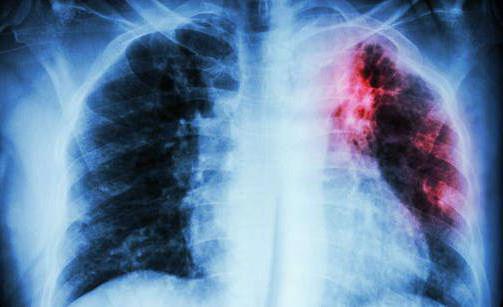

В большинстве случаев палочки Коха поражают легкие, но также существуют и другие виды недуга: туберкулез кишечника, гортани, мочеполовой системы, костей и кожи. Болезнь трудно поддается диагностике на начальных стадиях развития, что усложняет дальнейшее лечение. Прививка от туберкулеза способствует выработке антител и не дает развиться патогенным клеткам, попавшим в организм.

Положительная реакция на Д-тест у взрослого человека предполагает серьезное обследование. Пациенту показана рентгенологическая и лабораторная диагностика (в том числе проба Манту). Ребенку назначают рентгенографию легких (облучение при ней меньше, чем при флюорографии, а патологии легких просматриваются лучше). Это оправдано: по медицинским показаниям рентген показан даже женщинам в интересном положении.